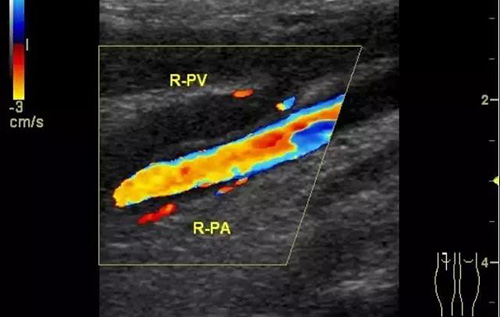

彩色多普勒超聲診斷儀_下肢深靜脈的彩超檢查

下肢深靜脈血栓形成后綜合征的診斷主要依靠靜脈造影和彩色超聲多普勒,而彩超機具有無創、重復性好、準確率高的優點,逐漸成為診斷此病的首選。

彩色普勒超聲診斷儀,線陣探頭,頻率7.5~10MHz。受檢查者先取仰臥位,患肢髖關節略外旋,大腿輕度外展且膝關節略曲,使整個下肢呈松弛狀態。自上而下順序檢查髂外、股總、股淺、股深及大隱靜脈;之后取俯臥位,檢查靜脈及小腿靜脈。以縱切和橫切顯示血管,灰階超聲主要觀察血管內徑、管壁結構及血栓情況,CDFI主要觀察管腔內有無血流顯示、充盈缺損及血液返流情況,必要時擠壓小腿腓腸肌以利血流顯示。

彩超診斷下肢深靜脈血栓形成后綜合征具有無創、實時、動態、重復性好、準確率高的特點,且能充分了解血管內外的解剖學改變,觀察靜脈管壁、血流充盈、靜脈瓣返流程度以及側支循環是否建立和血栓的溶液情況,可直觀地觀察到血流動力學改變,所以具有很高的使用價值。通過對治療前后聲像圖的對比,可以提示臨床的治療效果,對于臨床治療具有很大的指導作用。